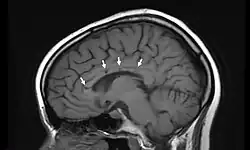

Vista lateral de una resonancia magnética nuclear de la cabeza. Las flechas indican la localización de microinfartos cerebrales característicos del síndrome de Susac. | ||

El síndrome de Susac en una rara enfermedad descrita en 1979 por el neurólogo norteamericano John Susac. Es una microangiopatía que provoca la oclusión de los pequeños vasos sanguíneos que aportan sangre al cerebro, la retina y el oído interno. Técnicamente se describe como una microangiopatía que afecta a las arteriolas precapilares. Los síntomas principales son dolor de cabeza, déficit cognitivo, pérdida de memoria, dificultad para la marcha, pérdida de visión y disminución de la capacidad auditiva (hipoacusia). La causa es desconocida, pero se cree que está provocado por un fenómeno de autoinmunidad. El tratamiento se basa en la administración de agentes inmunosupresores que disminuyen la respuesta inmunitaria, entre ellos glucocorticoides, azatioprina y metotrexate.[1][2][3][4]